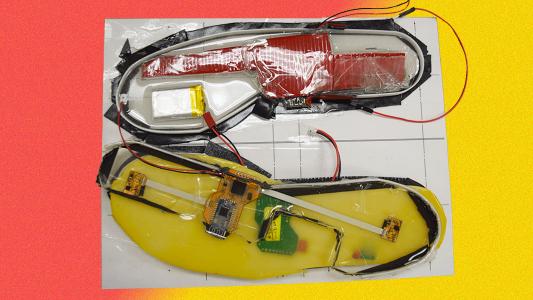

Shoe wearable could help Parkinson’s patients avoid falling

Data-collecting sensors in shoes can predict a Parkinson’s patient’s fall risk almost as accurately as standard walking tests.